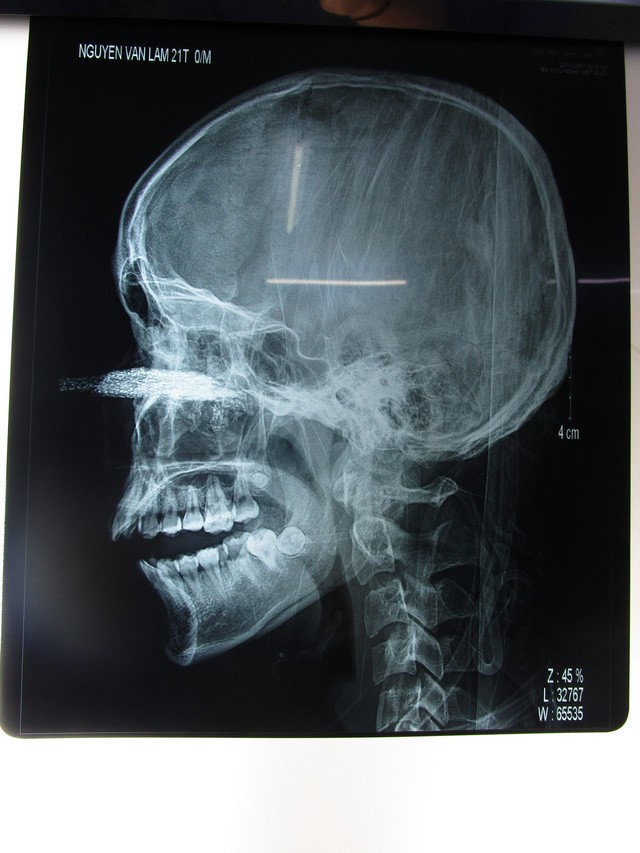

Hình ảnh chụp X-quang cho thấy lưỡi cưa đâm sâu vào bên trong - Ảnh: DânTrí

Sau ca phẫu thuật, bác sĩ lấy được 1 phần lưỡi cưa kích thước khoảng 10x12cm cắm sâu vào xoang hàm trên, có rất nhiều những dị vật nhỏ.